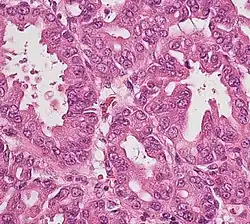

The most common form of pancreatic cancer (adenocarcinoma) is typically characterized by moderately to poorly differentiated glandular structures on microscopic examination. There is typically considerable desmoplasia or formation of a dense fibrous stroma or structural tissue consisting of a range of cell types (including myofibroblasts, macrophages, lymphocytes and mast cells) and deposited material (such as type I collagen and hyaluronic acid). This creates a tumor microenvironment that is short of blood vessels (hypovascular) and so of oxygen (tumor hypoxia).[2] It is thought that this prevents many chemotherapy drugs from reaching the tumor, as one factor making the cancer especially hard to treat.[2][3]

| Cancer type | Relative incidence[11] | Microscopy findings[11] | Micrograph | Immunohistochemistry markers[11] | Genetic alterations[11] |

| Pancreatic ductal adenocarcinoma (PDAC) | 90% | Glands and desmoplasia | ![]() |